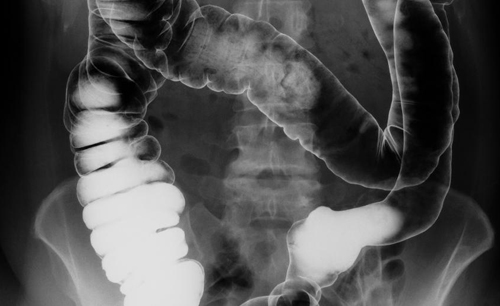

대장암은 신체 소화 기관의 마지막 부분인 대장에 발생하는 악성 종양을 가리킵니다. 대장은 결장과 직장으로 나뉘어 있는데요. 결장에 생기는 암을 결장암이라고 하고, 직장에 생기는 암을 직장암이라고 합니다. 이번에는 대장암 초기 증상에 어떤 것이 있는지 원인과 증상에 대해 살펴볼게요.

사실 대장암 초기증상은 무증상인 경우가 많은데요. 증상을 느껴서 병원에 찾아갔을 때는 이미 꽤 진행되었을 가능성이 있다고 해요. 대장암을 예방하려면 꾸준히 대장 내시경 검사를 하는 수밖에 없지만, 검사 과정과 검사 비용이 부담되어 소홀히 하는 사람도 많아요. 일단 대장암 초기증상을 잘 알아두고, 의심되는 경우 병원에 가서 진료를 받아야겠습니다.